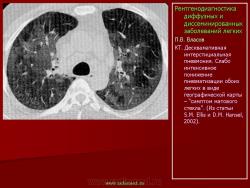

Основным методом выявления альвеолярного протеиноза является рентгенологическое исследование, причем наибольшей информативностью обладает компьютерная томография высокго разрешения. Классическими признаками являются симметричная альвеолярная консолидация или слабо интенсивное понижение пневматизации типа “матового стекла”. При локализации в прикорневых зонах изменения напоминают отек легких. На компьютерных томограммах 85 до 100% выявляется двустороннее слабоинтенсивное однородное затемнение большей или меньшей протяженности в виде матового стекла, по форме напоминающее географическую карту, на фоне которого виден сосудистый рисунок. Вторым по частоте признаком является очаговое уплотнение легочной ткани. Его частота составляет около 80%. В этих случаях в легочной ткани определяются либо мелкие очаговые или более массивные фокусные тенеобразования. В некоторых случаях картина напоминает диссеминацию милиарного типа. Реже (примерно в 7% случаев) встречается выраженный междольковый и внутридольковый фиброз. Характерным для этого заболевания считается также симптом “булыжной мостовой” (crazypaving) (B. Coulier с соавт., 1999; C.E. Engeler c cоавт., 1993; S. Murayama c соавт., 1999; J.S. Park с соавт., (1995); S.E. Rossi с соавт., 2003).

П.В. Власов